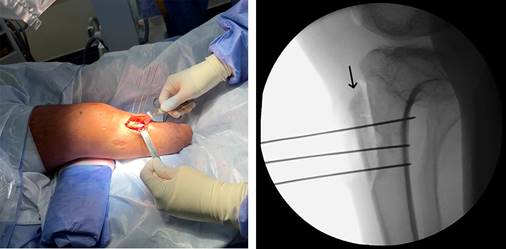

The patient was placed in a supine position under general anesthesia. Knee arthroscopy was performed through standard parapatellar portals to assess trochlear dysplasia and the integrity of the patellar cartilage, menisci, and cruciate ligaments. Subsequently, an approximately 4 cm vertical incision was made at the tibial tuberosity, and a complete tibial tubercle osteotomy (TTO) with distalization and medialization was performed (Figure 3). The osteotomy was fixed in its new position using three cannulated screws.